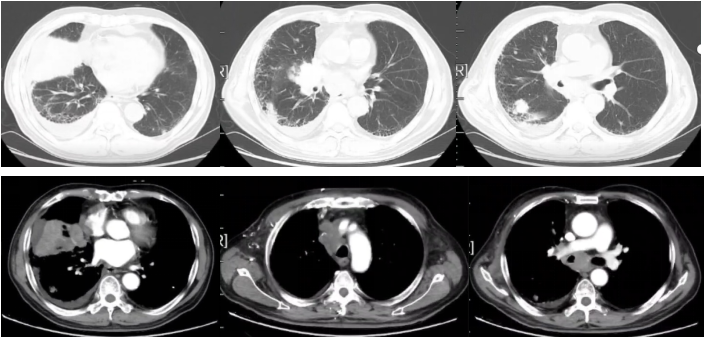

图3

2022-09-17胸部平扫CT:恶性肿瘤维持性化学治疗后,较2022-7-20胸部CT旧片,右肺中叶占位(7.3×4.4cm)缩小;双肺部分结节增大;纵隔及右肺门淋巴结缩小;主动脉左侧旁(2-22)淋巴结稍增大:右侧胸腔积液增多;左侧新增胸腔积液;胸壁水肿增厚,双侧腋窝小淋巴结,请结合临床;余未见显著变化。附见,胰尾较前稍增粗:肝S4段新增低密度小结节,请结合腹部相关检查。

疗效评价:SD。

2022-11-16胸部平扫CT:恶性肿瘤维持性化学治疗后,较2022-9-16日胸部CT,右肺中叶占位(2.2×1.9cm)缩小;双肺大部分结节消失;右侧胸腔积液减少,左侧胸腔积液消失;纵膈及双侧腋窝淋巴结缩小;扫描层面内肝脏结节本次未见明确显示,胰腺结节缩小;余较前变化不大。

疗效评价:PR。

2023-02-28胸部+上下腹增强CT:恶性肿瘤维持性化学治疗后,较2022-11-15日胸部CT,右肺中叶斑片影范围增大;右肺门淋巴结增大;右侧胸腔积液增多:心包积液减少;双肺间质性改变同前,余较前变化不大。胰尾旁多发结节,考虑MT可能。肝门区及腹膜后淋巴结稍大。左侧肾上腺结节样增厚,双侧部分肋骨、右侧髂骨高密度影,建议定期复查。肝S7段脂肪瘤。

图4